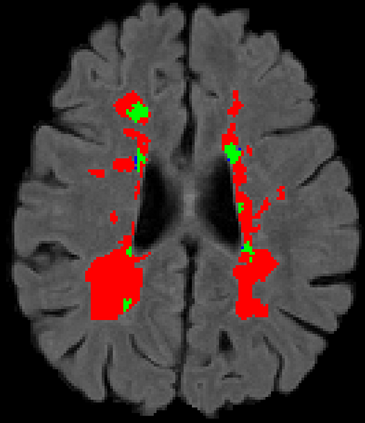

Recently, segmentation methods based on Convolutional Neural Networks (CNNs) showed promising performance in automatic Multiple Sclerosis (MS) lesions segmentation. These techniques have even outperformed human experts in controlled evaluation conditions such as Longitudinal MS Lesion Segmentation Challenge (ISBI Challenge). However state-of-the-art approaches trained to perform well on highly-controlled datasets fail to generalize on clinical data from unseen datasets. Instead of proposing another improvement of the segmentation accuracy, we propose a novel method robust to domain shift and performing well on unseen datasets, called DeepLesionBrain (DLB). This generalization property results from three main contributions. First, DLB is based on a large group of compact 3D CNNs. This spatially distributed strategy ensures a robust prediction despite the risk of generalization failure of some individual networks. Second, DLB includes a new image quality data augmentation to reduce dependency to training data specificity (e.g., acquisition protocol). Finally, to learn a more generalizable representation of MS lesions, we propose a hierarchical specialization learning (HSL). HSL is performed by pre-training a generic network over the whole brain, before using its weights as initialization to locally specialized networks. By this end, DLB learns both generic features extracted at global image level and specific features extracted at local image level. DLB generalization was validated in cross-dataset experiments on MSSEG'16, ISBI challenge, and in-house datasets. During experiments, DLB showed higher segmentation accuracy, better segmentation consistency and greater generalization performance compared to state-of-the-art methods. Therefore, DLB offers a robust framework well-suited for clinical practice.